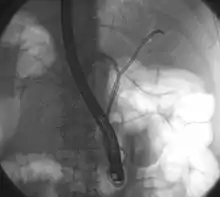

Klatskin tumor during ERCP. Wires were inserted into the left and right biliary systems. Both parts were injected through a tube with contrast, but there is no contrast visible in the area of confluence of the two systems